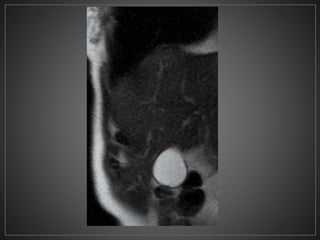

• #41 Adquisicion axial de R.M. ponderada en T2 con supresion grasa, donde se observa una imagen de morfologia ovalda, de bordes definidos, hiperintensa, en topografia de coledoco, en relacion a quiste de coledoco.